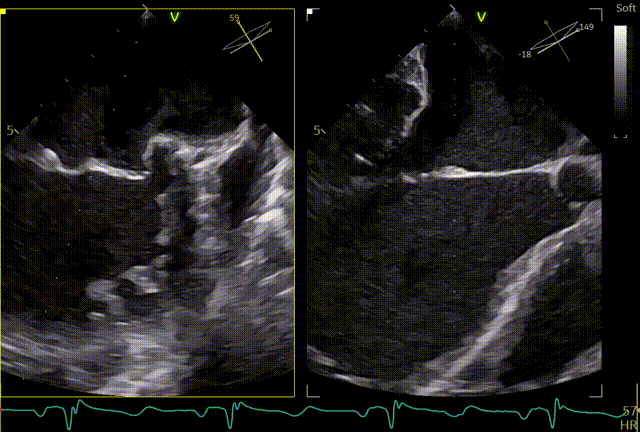

3D

3D带彩

3区gap

术前左房压